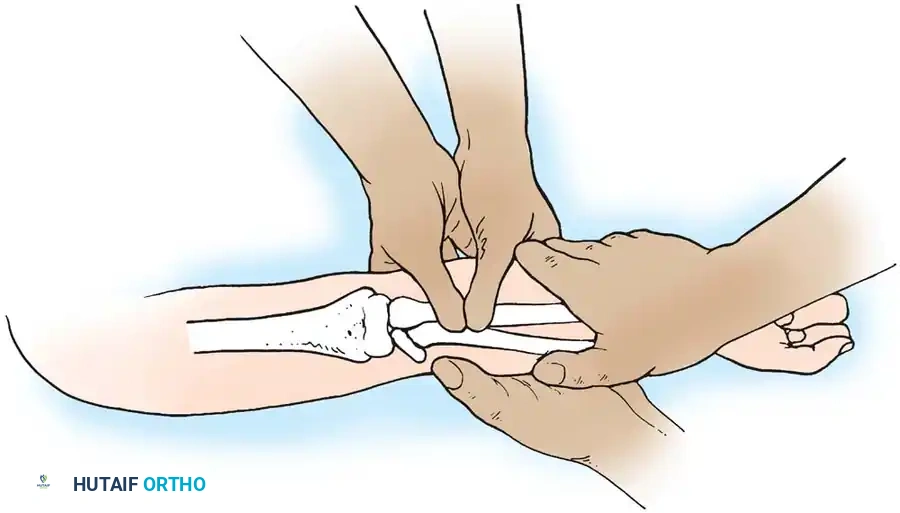

The Patterson Technique (Modified by Neher and Torch)

Fig. 33-42 Reduction technique for radial neck fractures.

- Positioning: The patient is placed supine. An assistant firmly stabilizes the distal humerus and the radius distal to the fracture site.

- Maneuver: With the elbow in full extension, the surgeon applies a strong varus stress to the elbow with one hand. This opens the radiocapitellar joint laterally.

- Reduction: Using the thumb of the opposite hand, direct lateral-to-medial pressure is applied over the tilted radial head to lever it back into anatomical alignment.

- Immobilization: The forearm is then placed in 90 degrees of flexion and pronation to lock the reduction.

Fig. 33-45 Mechanism of reduction of radial neck fracture.